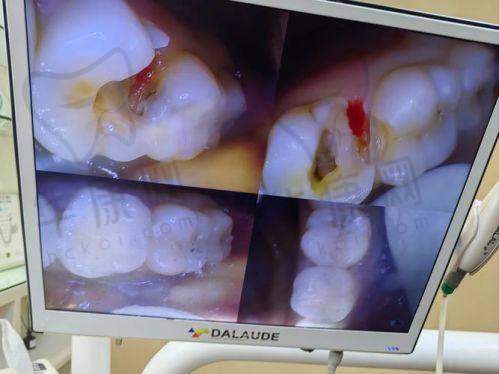

特别快我们就见到了医生。医生特别和蔼可亲,先温柔地和孩子聊了几句,让孩子放松下来,然后开始仔细地检查孩子的牙齿。医生用专精的仪器查看了牙齿的情况,还向我详细地解释了孩子牙齿龋坏的程度和原因。原来孩子平时爱吃甜食,又不注意好好刷牙,才导致牙齿出现了龋齿。医生说孩子的牙齿情况适合做树脂补牙,还给我介绍了几种不同的树脂材料,像Z250树脂、Z350树脂、3M进口树脂、美国进口树脂等,每种材料的特点和价格都不一样,让我可以根据自己的需求来选择。我考虑了一下,更终选择了3M进口树脂,价格是65元起。

确定好材料后,医生就开始给孩子补牙了。首先,医生给孩子的牙齿进行了清洁和消毒,这个过程孩子没有感觉到什么不舒服。然后,医生用专精的工具把龋坏的部分一点点地磨掉,孩子说有点酸酸的感觉,但还能忍受。接着,医生把调配好的3M进口树脂材料填充到牙齿的龋洞里,一边填充一边用仪器进行固化,让树脂和牙齿更好地结合。在这个过程中,医生的动作非常轻柔、熟练,还时不时地问孩子感觉怎么样,让孩子不要害怕。整个补牙过程大概用了半个小时左右,就顺利完成了。